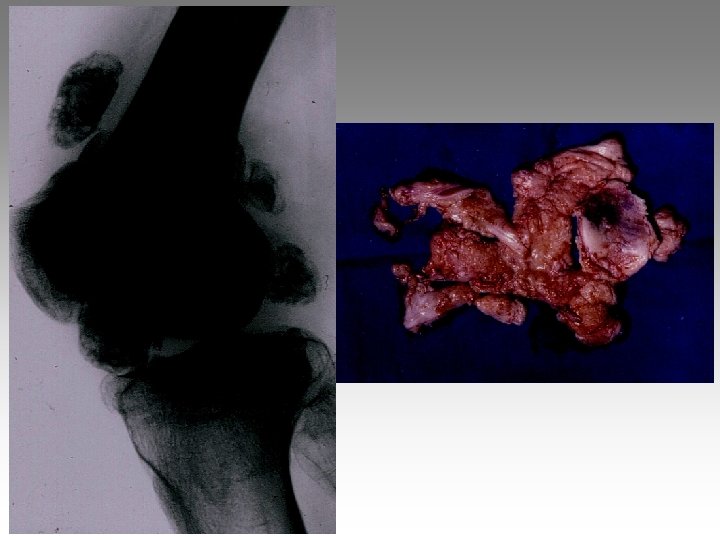

Hanche, T. , fract. fatigue Tendinites bursites, radic. Genou douloureux non traumatique Sémiologie Ponction +++ mécanique inflammatoire Rx inflammation Rx N Rx a. N < 40 ans interligne pincé Arthrose FT - FP contexte +++ > 40 ans Biologie, BS, Rx, IRM, écho interligne normal IRM AND, FF Paget, HOV ONA, OAN OAPH Ostéochond. infection IRM Arthroscopie Scinti. Os. LC Ménisque Coagul. PR, RP, Still, LED, SA…. Goutte, CCA AND ONA Ostéochondrite Pyogène, BK, Gono. , autres Hydarthrose X? Ostéochondromatose Synonite VN, T. , coag.

Genou douloureux non traumatique Sémiologie Ponction +++ mécanique inflammatoire Rx inflammation Rx N Rx a. N < 40 ans interligne pincé Arthrose FT - FP contexte +++ > 40 ans Biologie, BS, Rx, IRM, écho interligne normal IRM AND, FF Paget, HOV ONA, OAN OAPH Ostéochond. infection IRM Arthroscopie Scinti. Os. LC Ménisque Coagul. PR, RP, Still, LED, SA…. Goutte, CCA AND ONA Ostéochondrite Pyogène, BK, Gono. , autres Hydarthrose X? Ostéochondromatose Synonite VN, T. , coag.

Genou douloureux non traumatique Sémiologie Ponction +++ mécanique inflammatoire Rx inflammation Rx N Rx a. N < 40 ans interligne pincé Arthrose FT - FP contexte +++ > 40 ans interligne normal IRM AND, FF Paget, HOV ONA, OAN OAPH infection Biologie, BS, Rx, IRM, écho IRM Arthroscopie Scinti. Os. LC Ménisque Coagul. PR, RP, Still, LED, SA…. Goutte, CCA AND ONA Banal, BK, Gono. , autres Hydarthrose X? Ostéochondromatose Synonite VN, T. osseuse